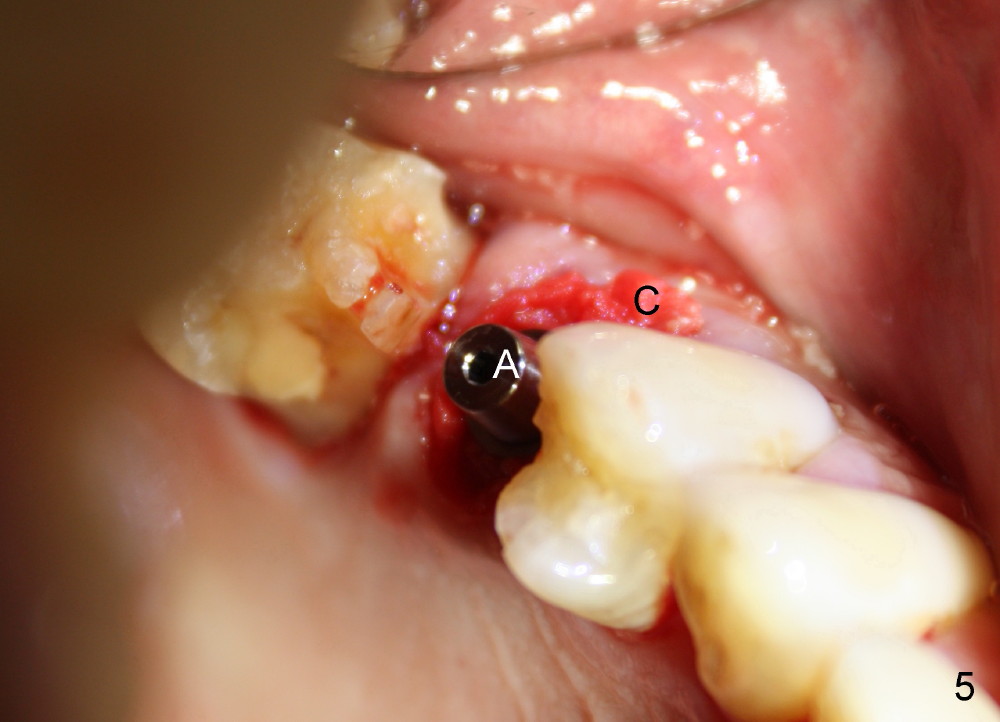

A 72-year-old man is a bruxer with #3 cusp fracture with chronic periapical radiolucency (Fig.1 *) and #4 acute crack. It appears reasonable to take care of emergency (#4 extraction and immediate implant (Fig.3-7: 4.5x20 mm, 45 Ncm)) followed by root canal therapy or extraction for #3. Eight (Fig.8) and 14 (Fig.9-11) days postop, the patient is doing fine and the wound heals normally. But he does not agree any treatment for #3, since it is asymptomatic in spite of a fistula associated with the tooth (Fig.8,9 >). Three months postop, the patient is still asymptomatic and is ready for #4 restoration since the tooth #28 cracks. Follow-up PA shows the persistent distal gap (Fig.12 >, as compared to Fig.4), accompanied with crestal bone resorption (*). Clinically the implant has mild mobility and light tenderness. The patient still refuses #3 treatment. It appears that the implant has failed to osteointegrate. In brief, do not place an immediate implant next to active infection.